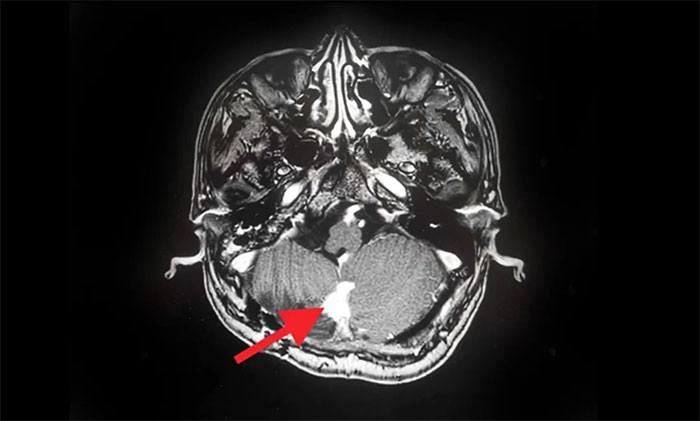

▲ MRI影像復(fù)查病灶明顯縮小

在伽瑪?shù)吨委熀,汪先生身體狀況良好,未出現(xiàn)明顯并發(fā)癥,經(jīng)綜合評(píng)估順利出院。8月份,他遵照醫(yī)囑來院復(fù)查,MRI可見病灶較治療前明顯縮小。

汪先生開心地談到,經(jīng)伽瑪?shù)吨委熀,頭痛癥狀明顯減輕,四肢麻木、行走不穩(wěn)也得到了改善。目前的他,對(duì)回歸正常生活充滿信心。